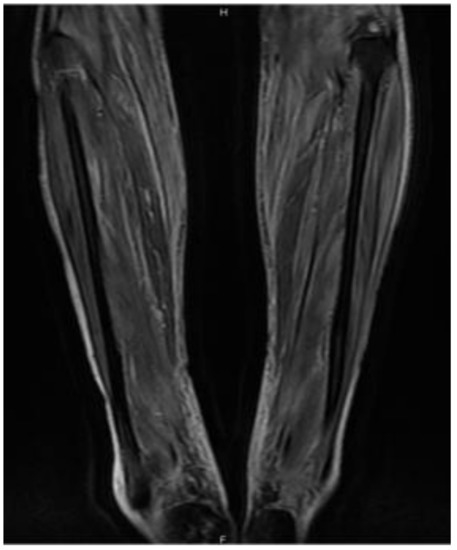

3.1. Case Report